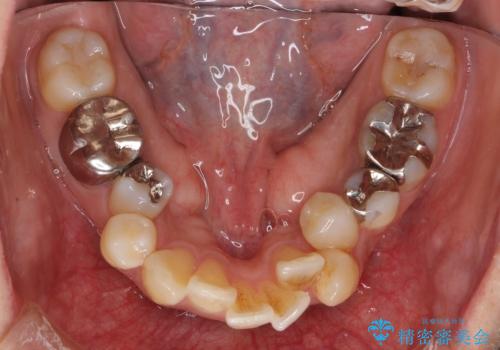

- 前歯のがたがた、出っ歯を主訴に来院。

がたつきは中等度で、上の前歯を下げるには歯を抜いてもスペースが不足していた為、上の奥歯を後ろに下げました。

下も混雑が激しく、歯を抜いてもスペースが不足していた為、下の前歯を少し削って小さくして並べています。